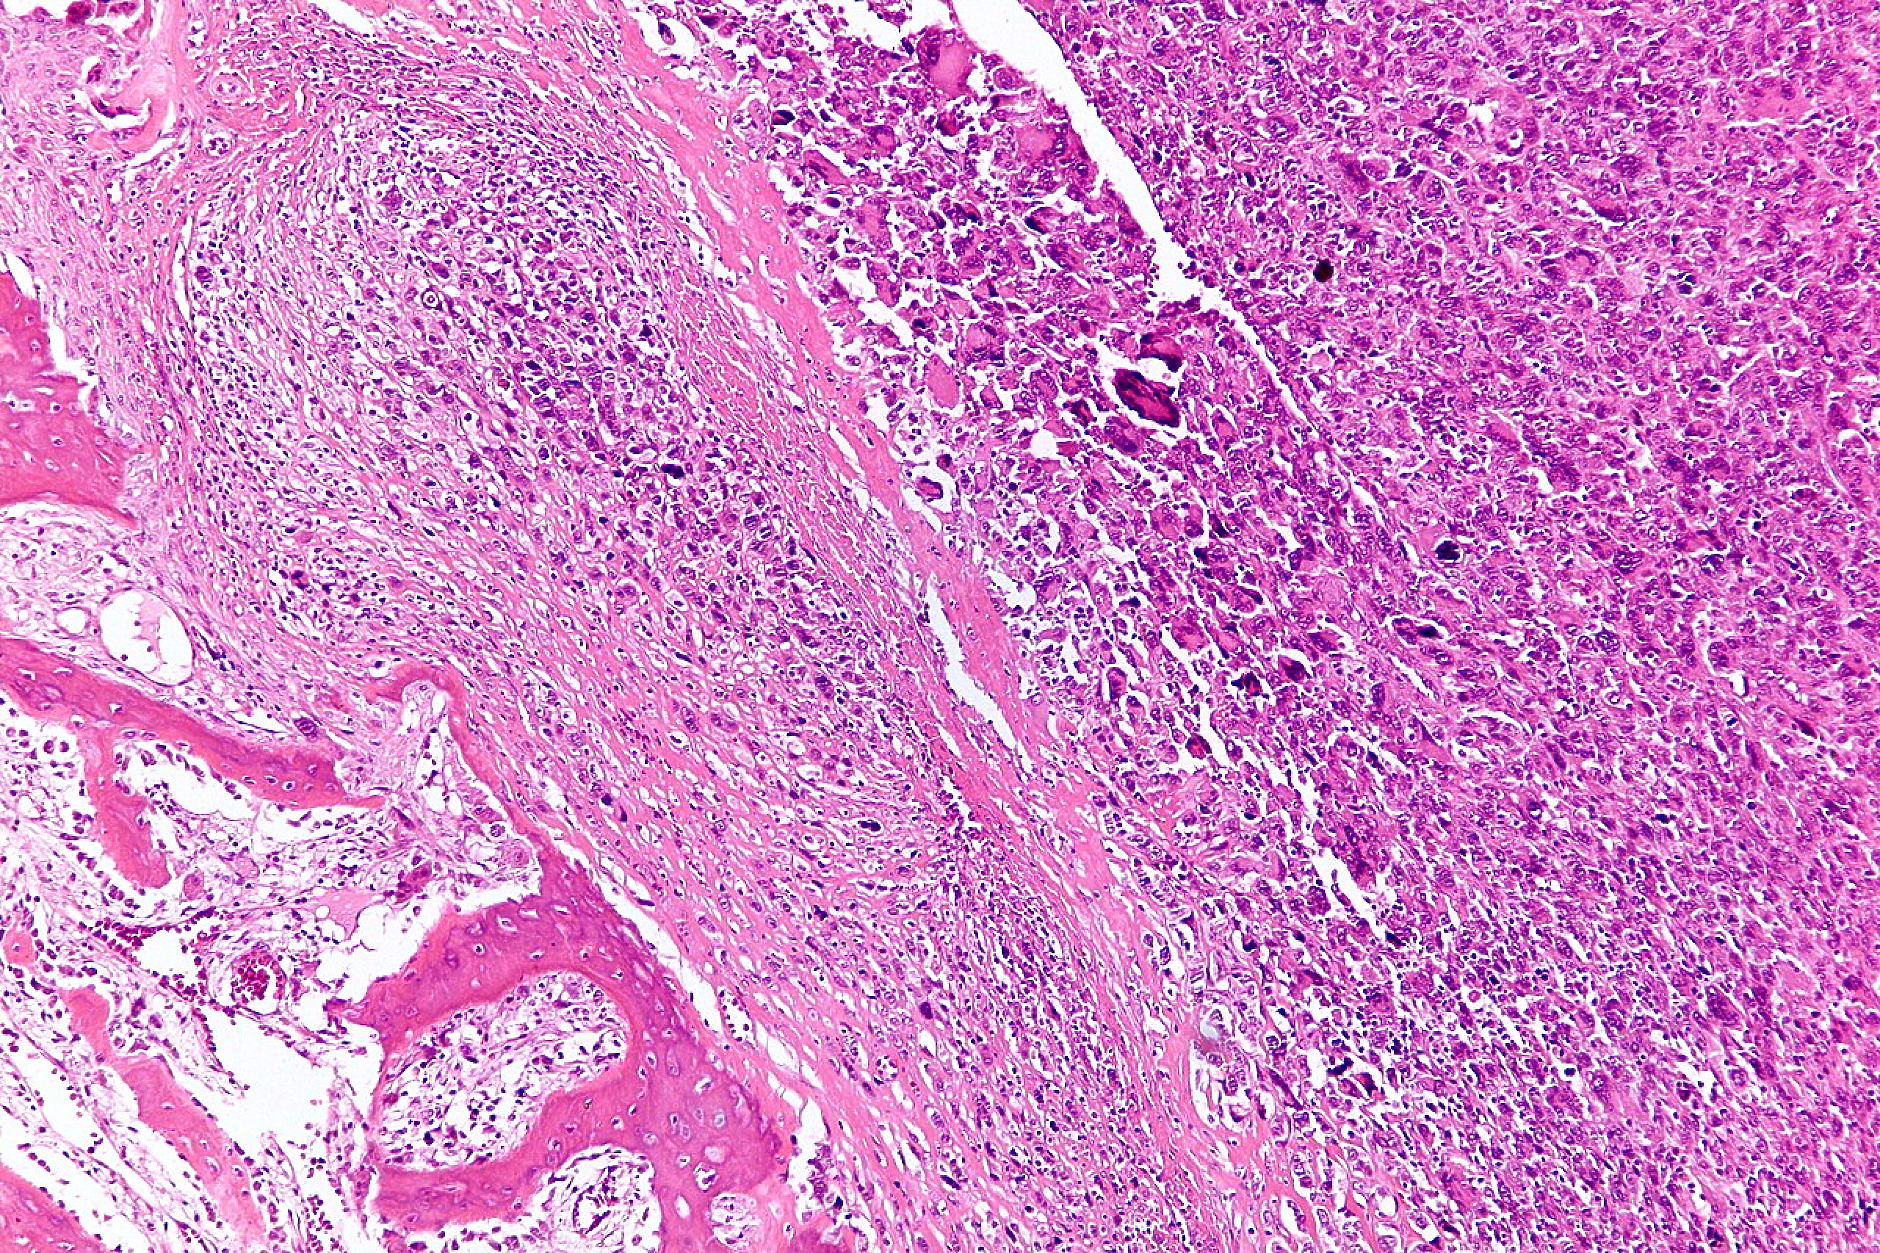

Изследователи от Бразилия и Португалия създадоха нов магнитен нанокомпозит, предназначен да атакува раковите клетки, засягащи костите, като същевременно подпомага възстановяването на костната система, съобщава онлайн изданието ScienceDaily. Работата, публикувана в Magnetic Medicine, описва структура „ядро–обвивка“, съставена от наночастици железен оксид, обвити с тънко покритие от биоактивно стъкло. Този дизайн позволява материалът да генерира топлина при излагане на магнитно поле, като остава здраво прикрепен към костната тъкан.

Ядрото от железен оксид придава на материала магнитни свойства. Когато се постави в променливо магнитно поле, то може да произведе локализирана топлина, достатъчно силна, за да увреди или унищожи раковите клетки. Този процес атакува туморната тъкан, като минимизира вредата върху близките здрави клетки.

В същото време покритието от биоактивно стъкло играе ключова роля в оздравяването. То стимулира околната костна тъкан да се регенерира, създавайки стратегия за лечение, която обединява премахването на тумора и структурния ремонт в една стъпка.